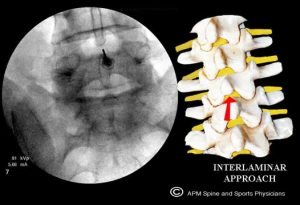

- Interlaminar ESI:the injection is usually midline and placed directly between two vertebrae (similar to the approach a woman undergoes during labor for epidural anesthesia). This approach is used less often as it delivers the steroid and lidocaine mixture to the

space behind the disc and is felt to be an older less direct approach. For this reason, this approach is used less often in the lower back but more often in the mid back and neck. - Transforaminal ESI or retro-discal ESI: with this ESI approach the spinal needle is placed into the foramina or opening for the nerve root on the same side of the spine as your pain and at the same level. Using X-ray guidance to steer the needle the Transforaminal approach directs the needle above the exiting nerve root and the retro-discal approach directs the needle below the exiting nerve and directly beh